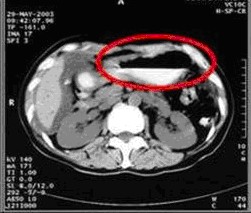

女,49歲。胃體癌晚期,胃竇增厚強(qiáng)化,與周?chē)尺B,腹膜增厚,腹腔廣泛轉(zhuǎn)移,伴大量腹水。放/化療失敗,無(wú)法手術(shù)。治療方案:腹腔灌注今又生2×1012VP/2次/周,共12周,同時(shí)灌注順鉑和5-氟尿嘧啶腹腔,后4周加8次全腹熱療。治療后:第3周,腹水消失;第8周,胃竇、腹膜和網(wǎng)膜變薄,盆腔結(jié)節(jié)明顯變小。后行手術(shù)切除殘余胃腫瘤,術(shù)中探查全腹和盆腔未捫及腫瘤。術(shù)后病檢胃腫瘤內(nèi)未見(jiàn)癌細(xì)胞。

治療前胃竇增厚強(qiáng)化,與周?chē)尘o,腹膜增厚,大量積水

治療中:第8周,腹水消失,胃壁變薄,盆腔結(jié)節(jié)明顯變小

治療結(jié)束:第12周,胃壁回復(fù)正常